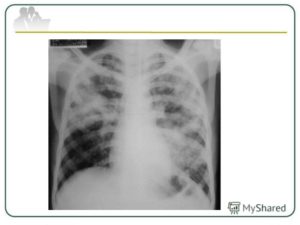

Рентген

Опасным воспалением при туберкулезе или пневмонии считается верхнедолевой очаг поражения, который чаще всего поражается микобактериями.

При пневмонии обнаруживаются на рентгене изменения, позволяющие отличить ее от туберкулеза:

- Уплотнение (инфильтрация) участка легких с неявными, размытыми очертаниями или в виде дымки (характерно для снимков при острой форме).

Флюорографией при пневмонии чаще выявляется поражение нижних и средних частей с изменениями корня легкого.

При туберкулезном инфицировании изменения отмечаются в верхней части легкого, отличаются четкими очертаниями, без видимых изменений корня.

На рентгенограмме обнаруживается при туберкулезе:

- Диссеминированном. Множество мелких, хорошо очерченных, или более крупных пятен, есть каверны.

- Очаговом. Уплотнение находится не ниже 2 ребра, вокруг могут быть фиброзные тяжи, усилен легочный рисунок.

- Инфильтративном. Уплотнения правильной округлой формы на рентгеновском снимке в верхней легочной доле.

- Казеозной пневмонии. Множество полостей распада с неровными краями, очагами отсева, смещением средостения в больную сторону груди.